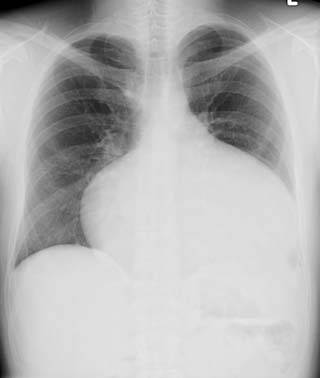

성인이 되어서 발견되는 경우도 있는데, 이때는 운동 시 호흡 곤란, 울혈성 심부전, 뇌졸중과 같은 뇌혈관 사고 등의 증상을 보이거나, 정기 검사에서 비정상적인 흉부 X-ray 또는 심전도 이상 소견이 나타나는 것이 계기가 될 수 있다.[36]

교정되지 않은 ASD가 있는 성인은 운동 시 호흡 곤란(가벼운 운동에도 숨이 참), 울혈성 심부전, 또는 뇌혈관 사고 (뇌졸중) 증상을 보인다. 정기적인 검사에서 비정상적인 흉부 X-ray 또는 비정상적인 심전도 소견을 보이며 심방 세동이 있을 수 있다. ASD가 좌우 단락을 유발하는 경우, 폐 혈관은 폐 혈류 증가로 인해 흉부 X-ray에서 확장된 것처럼 보일 수 있다.[36]

교정되지 않은 ASD가 있는 성인은 운동 시 호흡 곤란(가벼운 운동에도 숨이 참), 울혈성 심부전, 또는 뇌졸중과 같은 뇌혈관 사고 증상을 보일 수 있다. 정기 검진에서 비정상적인 흉부 X-ray나 심전도(ECG) 소견이 발견될 수 있으며, 심방 세동이 동반되기도 한다. ASD가 좌우 단락을 유발하는 경우, 폐 혈류 증가로 인해 흉부 X-ray에서 폐 혈관이 확장되어 보일 수 있다.[36]